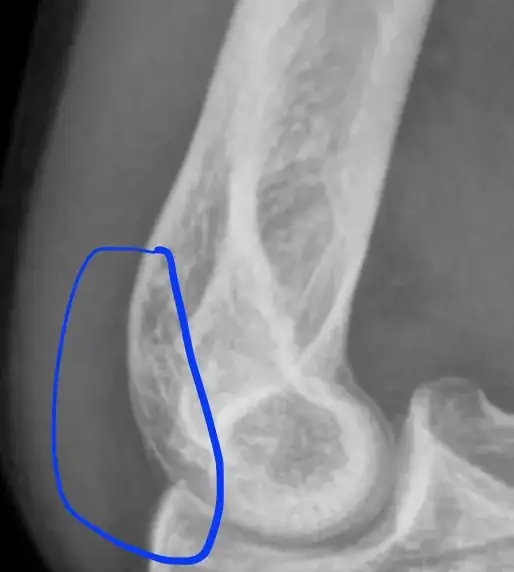

The Fracture is not an obvious one; there are occult fractures. The presence of a joint effusion, while not always associated with a fracture, is usually associated with a fracture when the history is consistent with an acute injury (possible fracture).

The radial head isn't grossly abnormal. There's a tiny suggestion of a possible fracture in the angularity of the radial neck. There 'should' be a bit of a smoother transition from the head to the radial shaft. However, it might not be called a fracture but for the presence of an effusion (in this case blood) in the joint capsule.

There are positive fat pad signs on the radiograph above.

If you look closely at the distal humerus, you'll see a shadow/lucency that shouldn't be there:

If you use your imagination, it looks like the sail of a sailboat traveling (?) westward. That's the sail sign.

If you look at the posterior humerus, you'll see a lucency all along the joint:

That's never present without an effusion. That's the posterior fat pad sign.

Without seeing more than one view, it's difficult to say where exactly the fracture is in the joint, but it's clear (if there's a history of recent trauma) that there's a fracture somewhere in the joint because of the two fat pad signs.